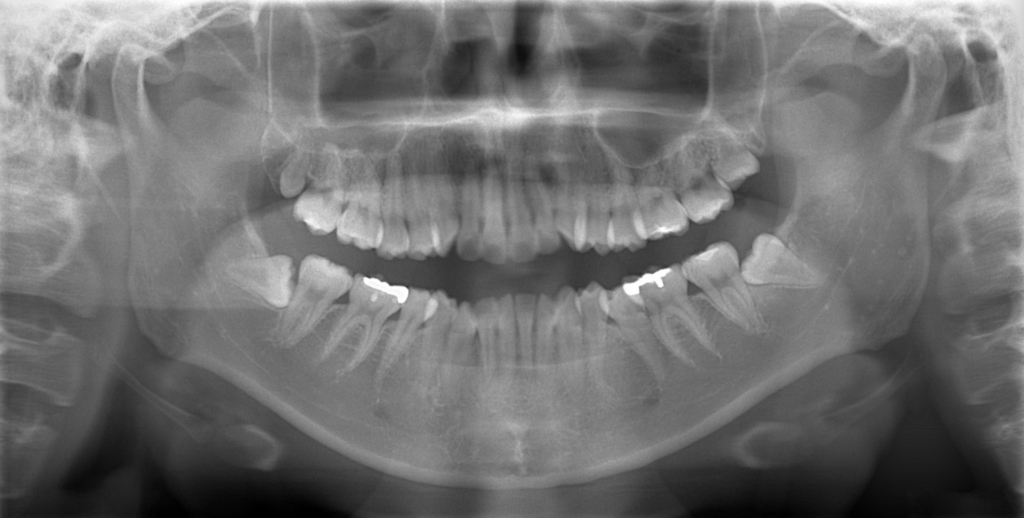

レントゲン写真でも比較してみましょう

左側が矯正治療前、右側が矯正治療後

【抜歯】

上下の左右の奥歯を1本ずつ計4本抜歯(すべて前から4番目の第一小臼歯を抜きました)

埋っている智歯は上下とも治療の早期に抜歯予定です